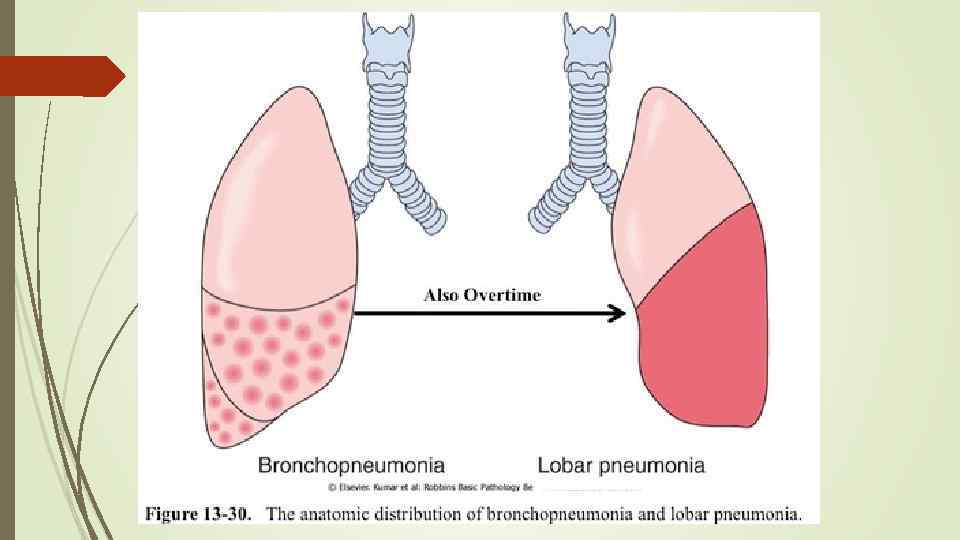

Классификация - по этиологии: бактериальные (с указанием возбудителя), вирусные, микоплазменные и риккетсиозные, аллергические, обусловленные физическими и химическими факторами этиологии; - по патогенезу: первичная, вторичная; - по морфологическим признакам: крупозная (долевая, фибринозная), очаговая (дольковая, бронхопневмония); - по течению: остротекущая, затяжная.

Классификация - по этиологии: бактериальные (с указанием возбудителя), вирусные, микоплазменные и риккетсиозные, аллергические, обусловленные физическими и химическими факторами этиологии; - по патогенезу: первичная, вторичная; - по морфологическим признакам: крупозная (долевая, фибринозная), очаговая (дольковая, бронхопневмония); - по течению: остротекущая, затяжная.

Классификация очаговой — то есть занимать небольшой очаг лёгкого (бронхопневмония — респираторные отделы+бронхи) сегментарной — распространяться на один или несколько сегментов лёгкого, долевой — захватывать долю лёгкого. Классическим примером долевой пневмонии является крупозная пневмония — преимущественно альвеолы и прилежащий участок плевры. сливной — слияние мелких очагов в более крупные. тотальной — пневмония называется, если она распространяется на всё лёгкое. Кроме того, пневмония может быть односторонней, если поражено только одно лёгкое, и двусторонней, если больны оба лёгких.

Классификация очаговой — то есть занимать небольшой очаг лёгкого (бронхопневмония — респираторные отделы+бронхи) сегментарной — распространяться на один или несколько сегментов лёгкого, долевой — захватывать долю лёгкого. Классическим примером долевой пневмонии является крупозная пневмония — преимущественно альвеолы и прилежащий участок плевры. сливной — слияние мелких очагов в более крупные. тотальной — пневмония называется, если она распространяется на всё лёгкое. Кроме того, пневмония может быть односторонней, если поражено только одно лёгкое, и двусторонней, если больны оба лёгких.

Бронхопневмония (дольковая, катаральная, очаговая пневмония) Поражение стенки легочная паренхима бронхов Эндобронхит панбронхит пневмонический фокус

Бронхопневмония (дольковая, катаральная, очаговая пневмония) Поражение стенки легочная паренхима бронхов Эндобронхит панбронхит пневмонический фокус

Бронхопневмония Характерно наличие двухсторонних множественных очаговых теней. Контуры очагов нечеткие, интенсивность тени небольшая. Инфильтрация неоднородна. Мелкие, малоинтенсивные очаги не всегда выявляются на снимках. Легочный рисунок усилен на всем протяжении легких. Корни расширены, не структурны. Как правило, отмечается реакция плевры, могут быть и экссудативные плевриты.

Бронхопневмония Характерно наличие двухсторонних множественных очаговых теней. Контуры очагов нечеткие, интенсивность тени небольшая. Инфильтрация неоднородна. Мелкие, малоинтенсивные очаги не всегда выявляются на снимках. Легочный рисунок усилен на всем протяжении легких. Корни расширены, не структурны. Как правило, отмечается реакция плевры, могут быть и экссудативные плевриты.